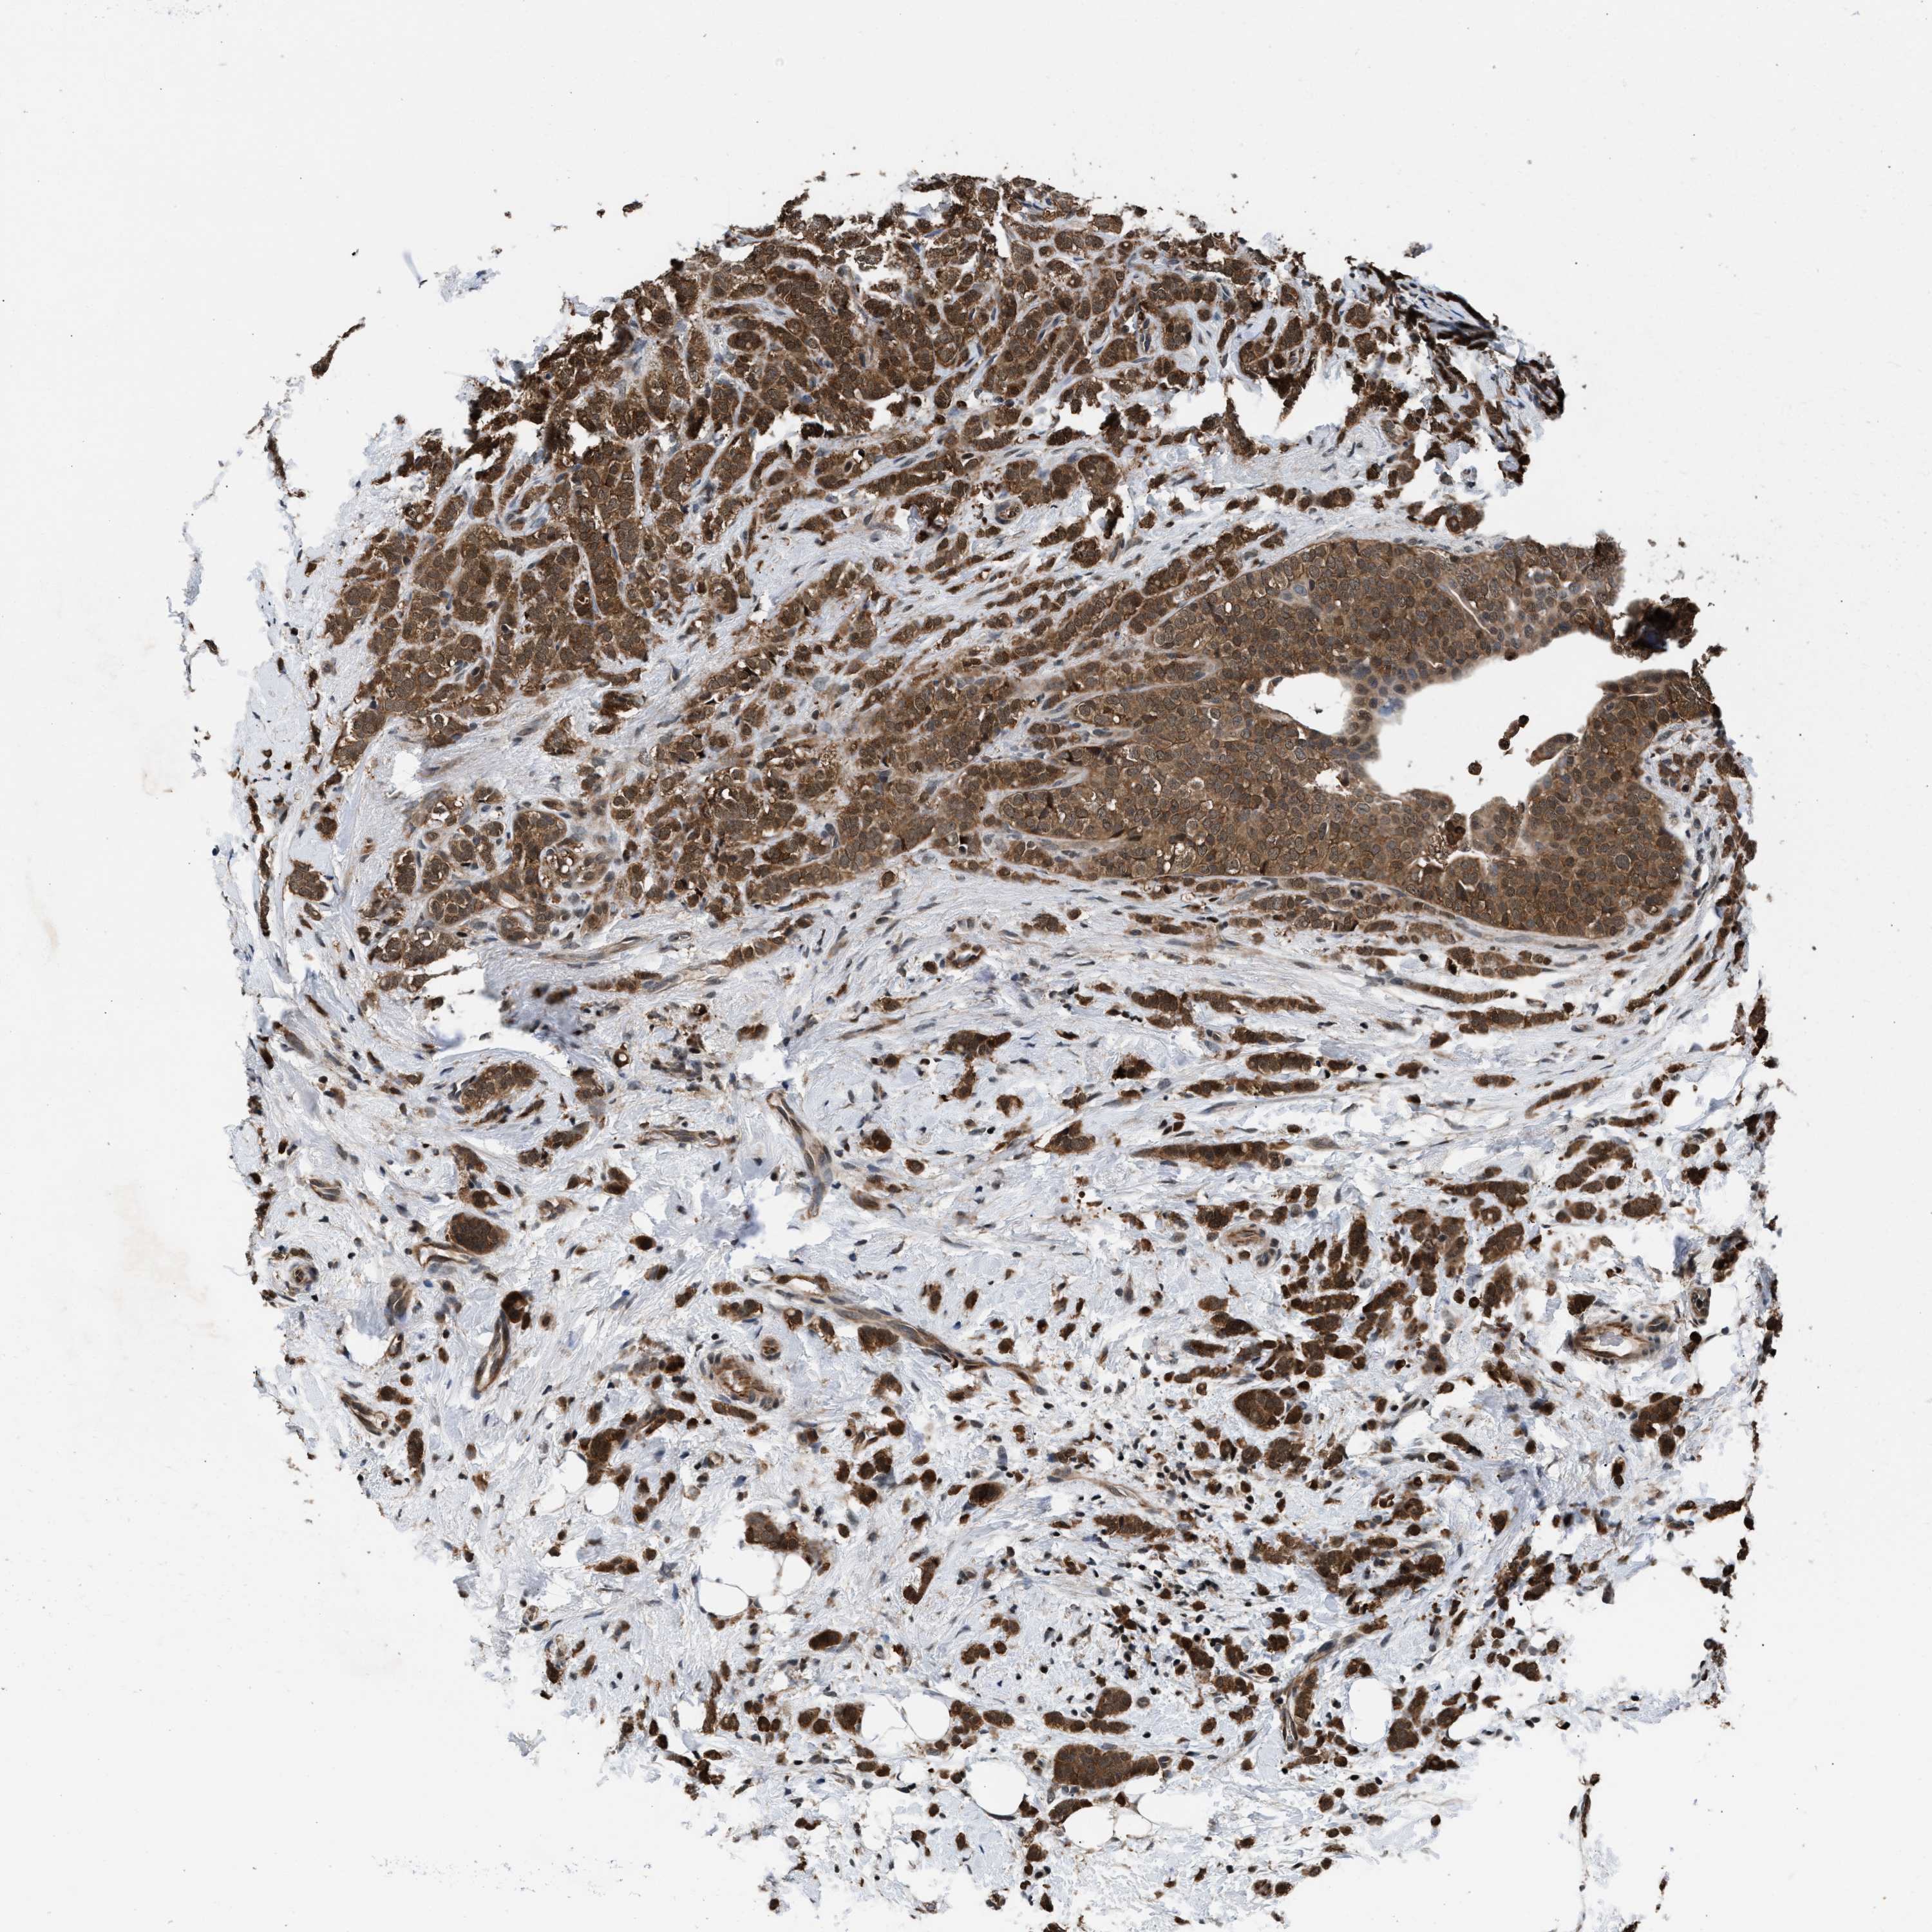

CANCER BREAST CANCER Show tissue menu

BRCA TCGA BRCA VALIDATION PROTEIN EXPRESSION